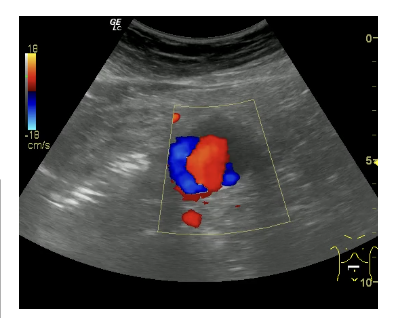

Informe: Hígado de tamaño y ecogenicidad normal. Vesícula distendida con 2 litiasis de 2 x 3 mm en su interior. Páncreas y bazo de ecoestructura normal. Ambos riñones de tamaño, ecogenicidad en rango, diferenciación corticosinusal. Vena porta, cava inferior y aorta en el área del lóbulo hepático izquierdo de calibre normal. Aneurisma de aorta abdominal descendente hasta su bifurcación de ambas iliacas de 3.29 cm en su eje trasversal con engrosamiento de pared posterior.

• Aneurisma de aorta abdominal.

Desde el seguimiento realizado por el Servicio de Cirugía vascular se observa un crecimiento paulatino de 0,6 cm en 6 meses por lo que se decide intervenir quirúrgicamente.